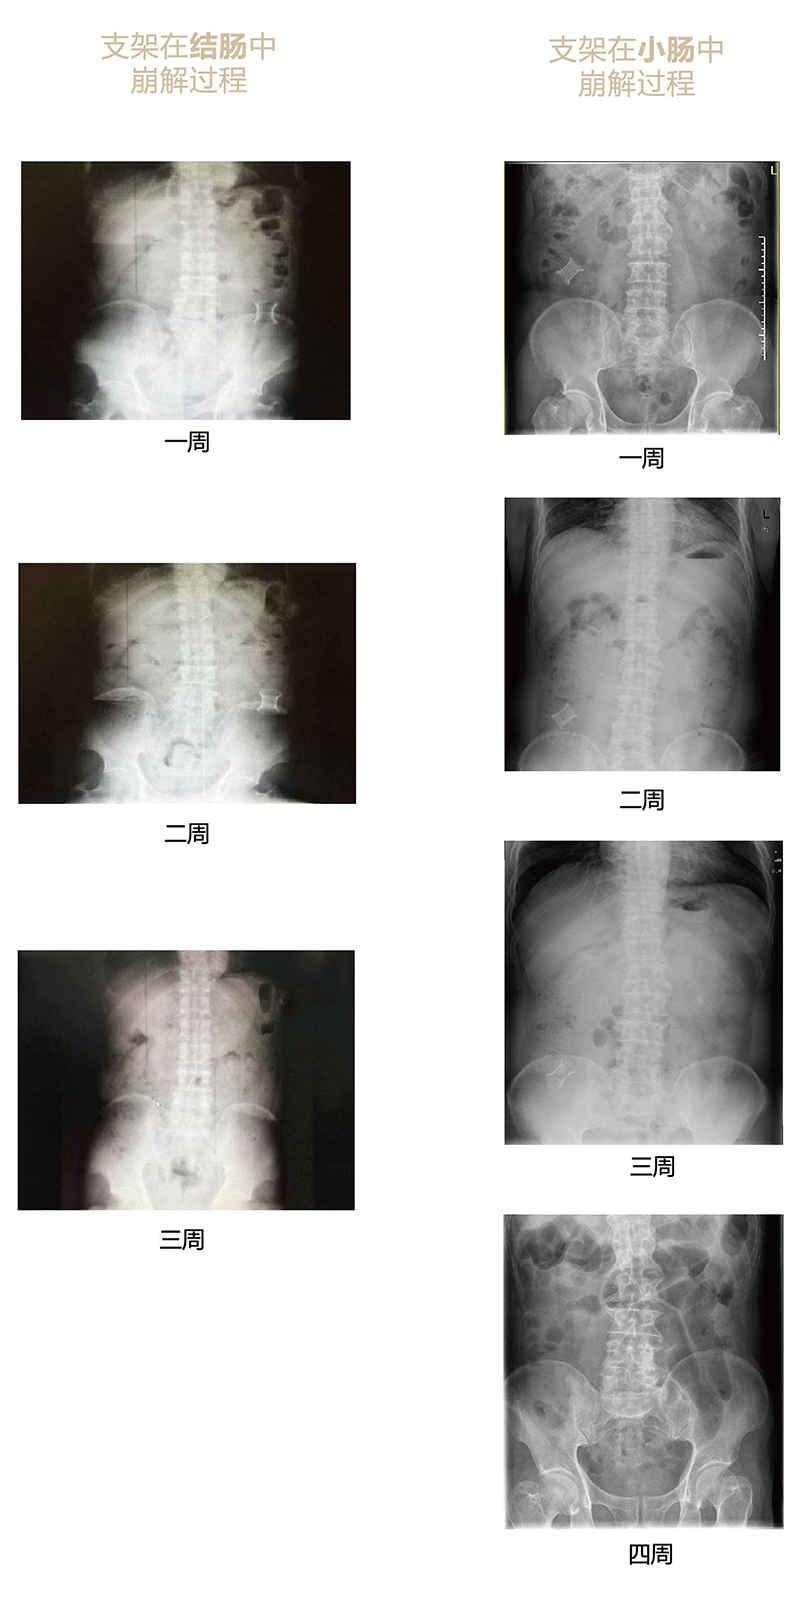

“可崩解腸道吻合器”由聚乙醇酸(PGA)與硫酸鋇按重量比7:1混合注塑制成,在X線下顯影,可動態追蹤可崩解腸道吻合器(支架)在腸道內崩解過程。

為解決該問題,蔡秀軍教授在“支架法空腔臟器吻合技術”的理念基礎上,又發明了“蔡氏腸轉流術”,這是一種應用“可崩解腸道吻合器HB型(可崩解腸轉流支架)”(發明專利號:201910794214.3),的支架法腸道轉流術,此創新術式既能保護低位吻合口,更避免了回納術。可崩解腸轉流支架在直腸癌根治術中植入遠端回腸,可確保完全阻斷腸腔,用腸造瘺管在轉流支架近端行腸造瘺,起到完全轉流的作用。腸轉流支架在二至三周內逐漸崩解,并在四周內完全排出體外,恢復腸道通暢后拔除造瘺管,避免了傳統造口回納的二次手術。該創新術式具有方法簡單、吻合時間短、人體內無異物永久殘留、不破壞吻合口粘膜下血管,并能預防吻合口漏、可避免人工肛門留置及二次手術、治療周期可縮短至二至四周、患者生理心理創傷顯著減少。